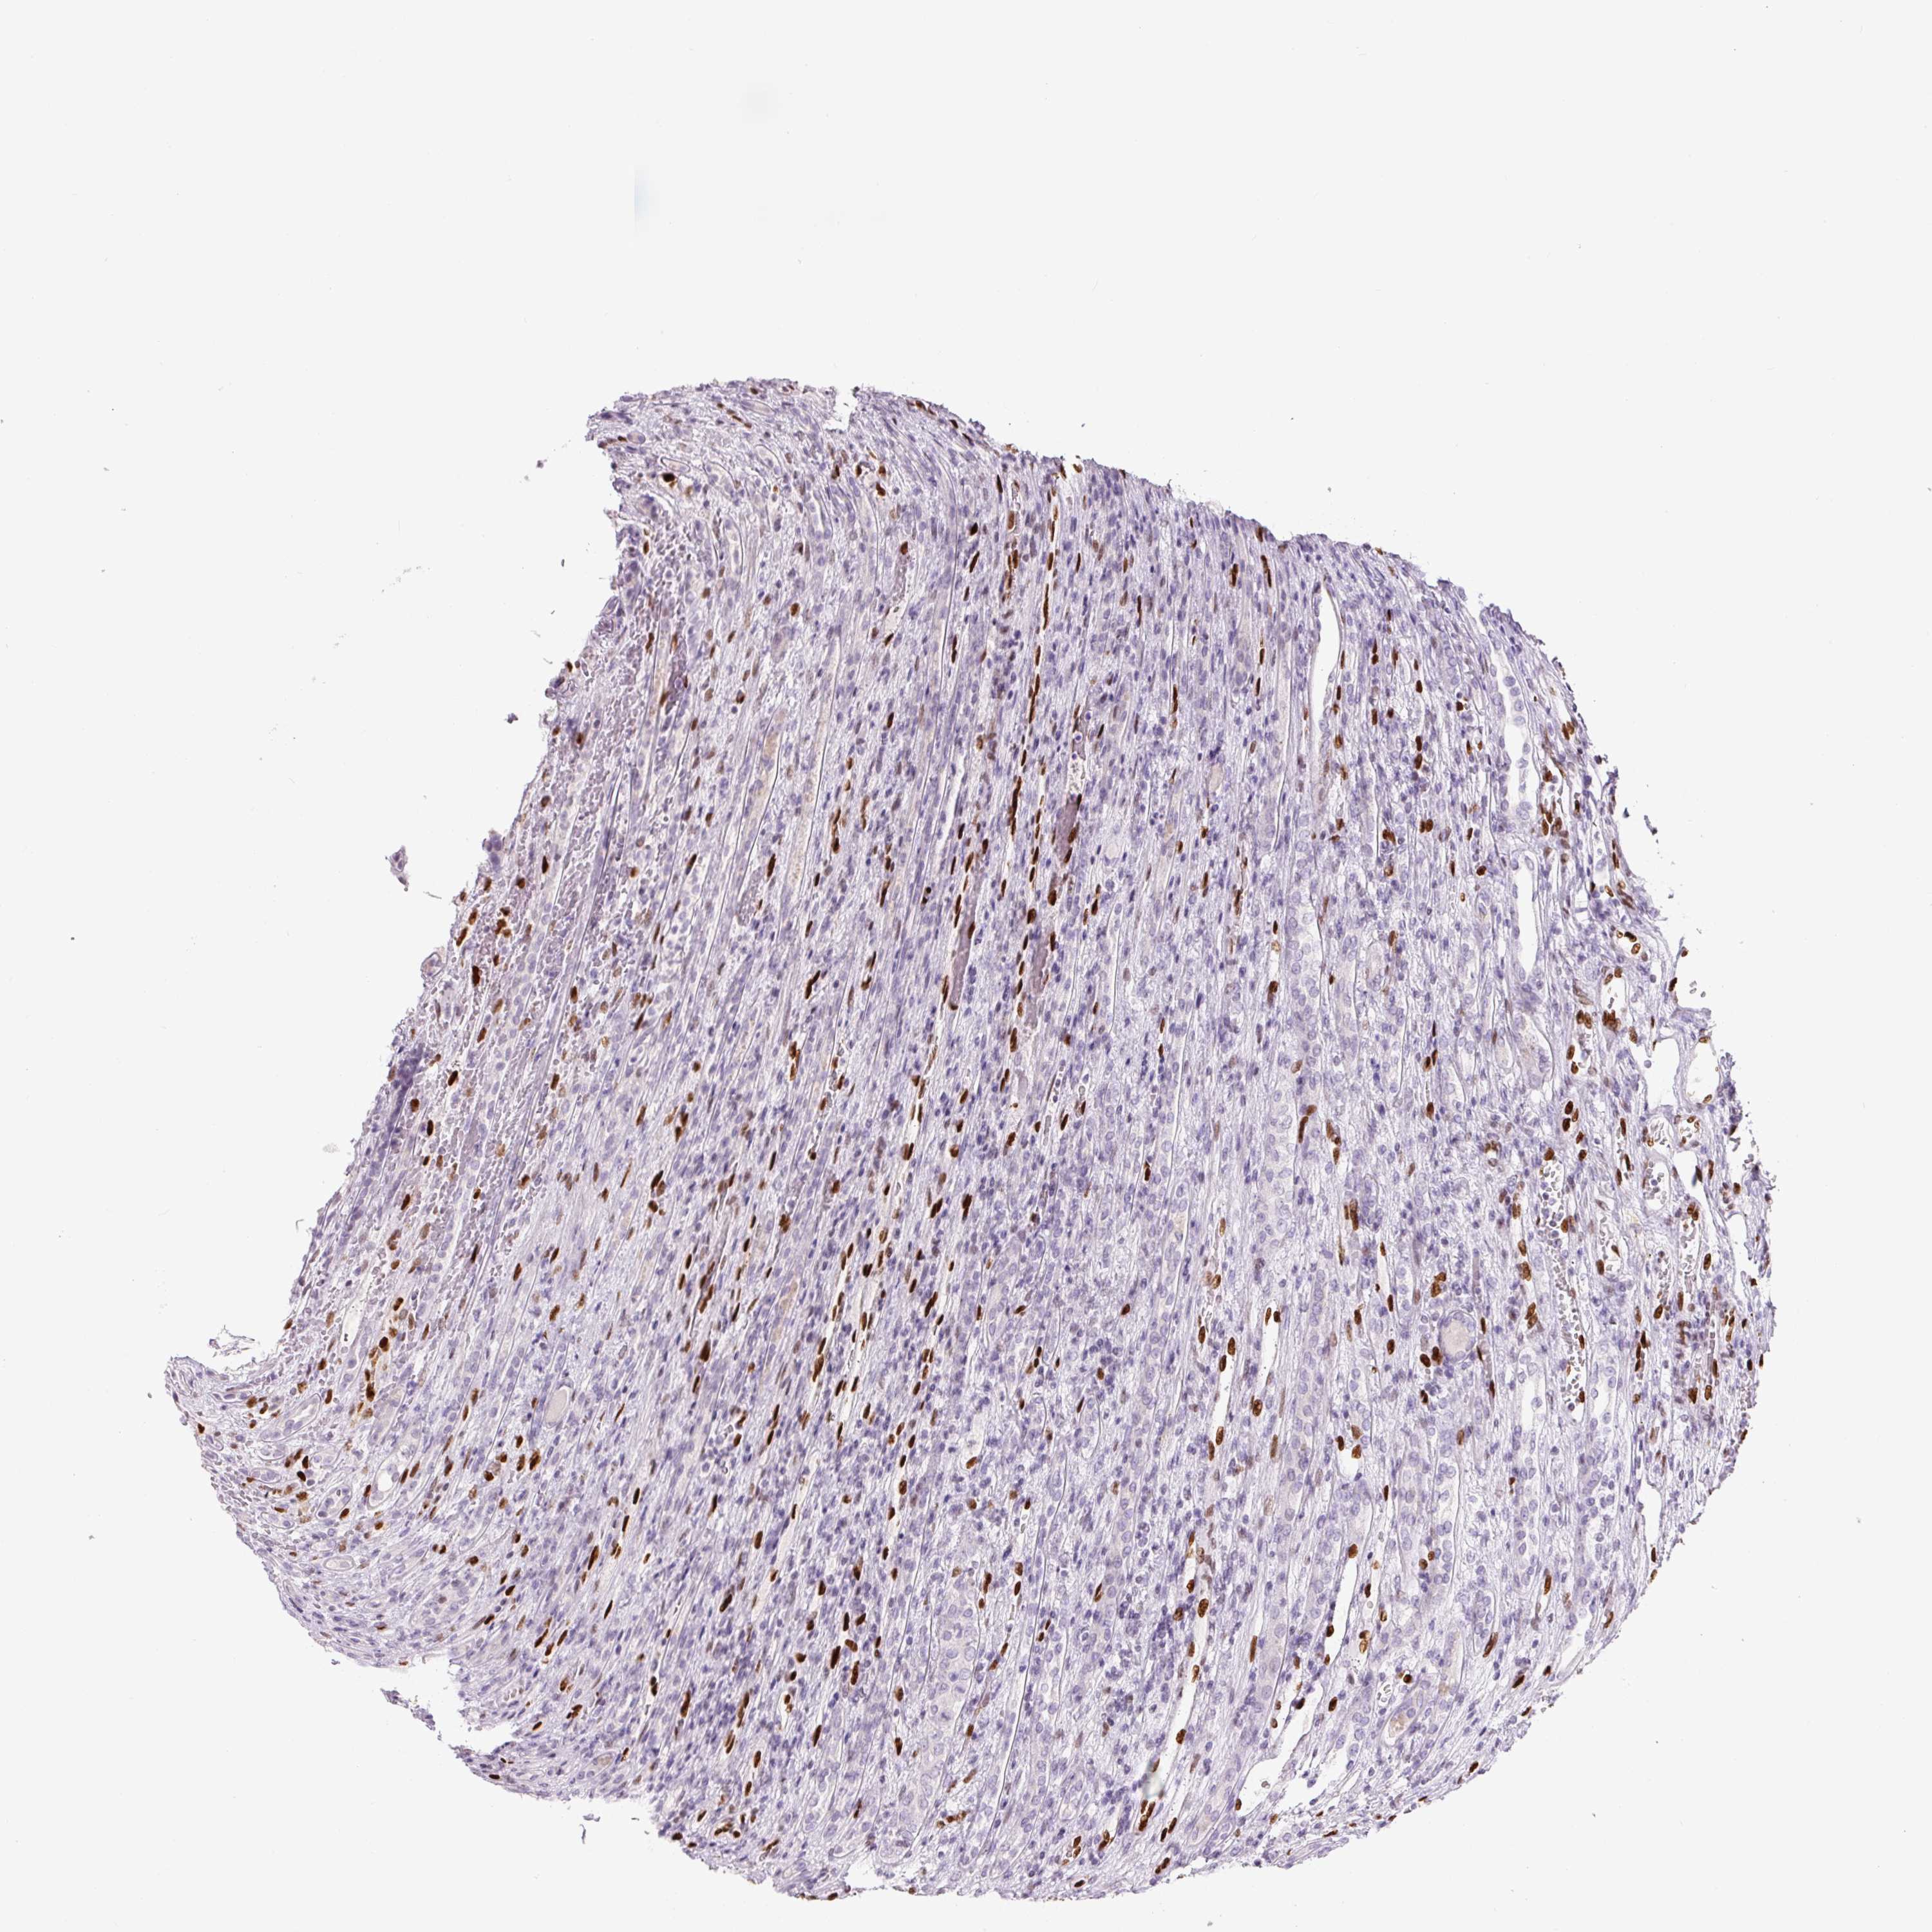

KIDNEY RENAL CLEAR CELL CARCINOMA (VALIDATION) - Interactive survival scatter ploti

The Survival Scatter plot shows the clinical status (i.e. dead or alive) for all individuals in the patient cohort, based on the same data that underlies the corresponding Kaplan-Meier plots. Patients that are alive at last time for follow-up are shown in blue and patients who have died during the study are shown in red.

The x-axis shows the expression levels (FPKM) of the investigated gene in the tumor tissue at the time of diagnosis. The y-axis shows the follow-up time after diagnosis (years). Both axes are complimented with kernel density curves demonstrating the data density over the axes. The top density plot shows the expression levels (FPKM) distribution among dead (red) and alive patients (blue). The right density plot shows the data density of the survived years of dead patients with high and low expression levels respectively, stratified using the cutoff indicated by the vertical dashed line through the Survival Scatter plot. This cutoff is automatically defined based on the FPKM cutoff that minimizes the p-score. The cutoff can be changed by dragging the vertical line or by entering a cutoff value in the square labeled "Current cut-off".

Under the Survival Scatter plot the p-score landscape (black curve; left axis) is shown together with dead median separation (red curve; right axis). Dead median separation is the difference in median mRNA expression between patients who have died with high and low expression, respectively. It is calculated as follows: median FPKM expression of dead patients with high expression - median FPKM expression of dead patients with low expression. This is intended to aid the user in visually exploring custom cutoffs and the associated p-scores and dead median separation.

Individual patient data is displayed and can be filtered by clicking on one or more of the category buttons on the top of the page. Categories describing expression level and patient information include: high, low, alive, dead, female, male and tumor stages. The scale of the x-axis can be toggled between linear and log-scale by clicking on the "x log" button. Mouse-over function shows TCGA ID, patient information and mRNA expression (FPKM) for each patient.

& Survival analysisi

Kaplan-Meier plots summarize results from analysis of correlation between mRNA expression level and patient survival. Patients were divided based on level of expression into one of the two groups "low" (under cut off) or "high" (over cut off). X-axis shows time for survival (years) and y-axis shows the probability of survival, where 1.0 corresponds to 100 percent.

ZEB1 is validated prognostic, high expression is favorable in Kidney Renal Clear Cell Carcinoma (validation)

Best expression cut offi

Based on the FPKM value of each gene, patients were classified into two groups and association between prognosis (survival) and gene expression (FPKM) was examined. The best expression cut-off refers the FPKM value that yields maximal difference with regard to survival between the two groups at the lowest log-rank P-value. Best expression cut-off was selected based on survival analysis .

When clicking on this number, the vertical dashed line indicating cut-off, the interactive survival plot, and the Kaplan-Meier curve will be adjusted to show results based on the best expression cut-off.

: 18.06

Median expressioni

Median expression refers to the median FPKM value calculated based on the gene expression (FPKM) data from all patients in this dataset. When clicking on this number, the vertical dashed line indicating cut-off, the interactive survival plot, and the Kaplan-Meier curve will be adjusted to show results based on the median expression.

: N/A

Median follow up timei

Median follow up time refers to the median time (years) after diagnosis with this type of cancer, based on clinical data from all patients in this dataset.

P scorei

Log-rank P value for Kaplan-Meier plot showing results from analysis of correlation between mRNA expression level and patient survival.

N/A

5-year survival highi

5-year survival for patients with higher expression than the expression cutoff.

For melanoma and glioma, 3-year survival is shown.

5-year survival lowi

5-year survival for patients with lower expression than the expression cutoff.

TCGA RNA samplesi

RNA-seq data is reported as average FPKM (number Fragments Per Kilobase of exon per Million reads), generated by the The Cancer Genome Atlas (TCGA) .

Normal distribution across the dataset is visualized with box plots, shown as median and 25th and 75th percentiles. Points are displayed as outliers if they are above or below 1.5 times the interquartile range. FPKM values of the individual samples are presented next to the box plot.

Average pTPM 18.2

Number of samples 100